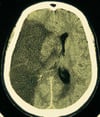

Снижение дифференцировки коры островка

На этой КТ-снимке показано снижение дифференцировки в области сильвиевой борозды и островка (прямые стрелки) на пораженной стороне мозга по сравнению с нормальным ребристым видом коры островка (изогнутые стрелки).

By permission of the publisher. From Geremia G, Greenlee W. In Atlas of Cerebrovascular Disease. Edited by PB Gorelick and MA Sloan. Philadelphia, Current Medicine, 1996.